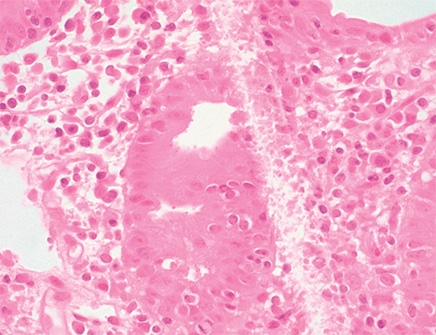

In Fig. 8 small basophilic bodies are seen on the luminal surface of the enterocytes, and thus the differential diagnosis includes infectious parasitic organisms such as Cyclospora cayetanensis, Cystoisospora (Isospora) belli, Cryptosporidium, and Microsporidium. “The first three are members of Coccidia, which is a subclass of microscopic spore-forming, single-celled, obligate intracellular parasites that can infect epithelial cells lining the digestive tract of humans and animals,” Dr. Iuga explained. On histology, they are usually distinguished by size and location. Cryptosporidium (4–6 µm) is usually located at the luminal surface of the enterocytes. Cystoisospora is larger, averaging 20 to 30 µm in size, and Cyclospora measures 8 to 10 µm. They are usually observed inside the enterocytes. “Microsporidia, which average 1.5 to 2 µm, were formerly considered spore-forming protozoa and have been reclassified as intracellular fungi.”

Cryptosporidium organisms show small basophilic round bodies protruding from the apex of enterocytes, highlighted with Giemsa stain. “Interestingly, they are considered intracellular but extracytoplasmic in location,” Dr. Iuga said. They are located within parasitophorous vacuoles covered by the host’s microvillous membranes. “Histologically,” she said, “the small intestine mucosa can show variable villous atrophy, variable inflammation including cryptitis and lamina propria neutrophilic infiltrate, as well as intraepithelial lymphocytosis and eosinophil infiltrate.”